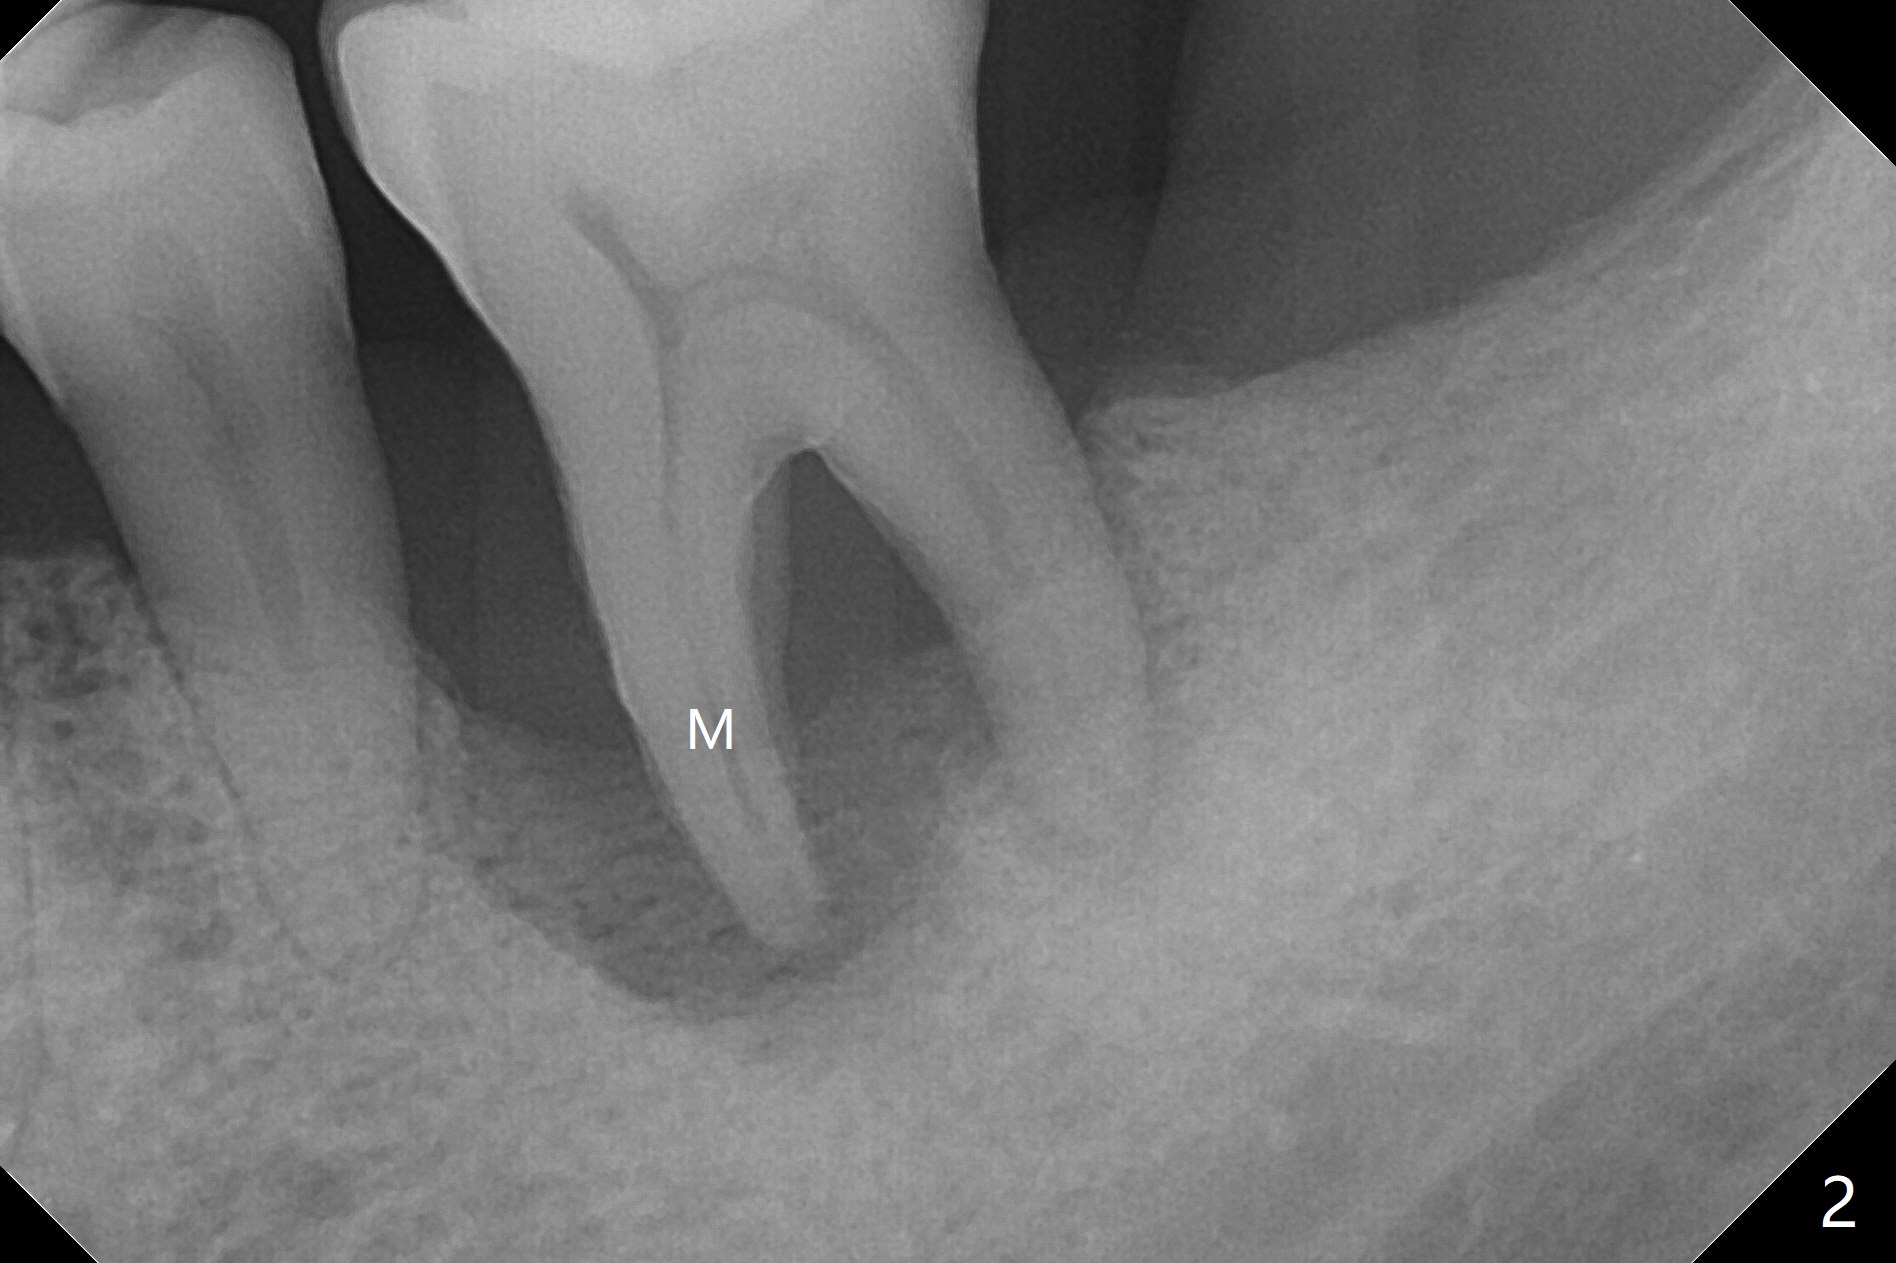

A 50-year-old man (smoker, bruxer (also missing the tooth #2 and 3)) requests extraction of the tooth #19 with mobility and buccal gingival infection (Fig.1 *). There is severe bone loss around the mesial root (Fig.2 M). It appears that the soft tissue (Fig.3 *) prevents the bone graft from being deposited in the distal surface of the neighboring root.